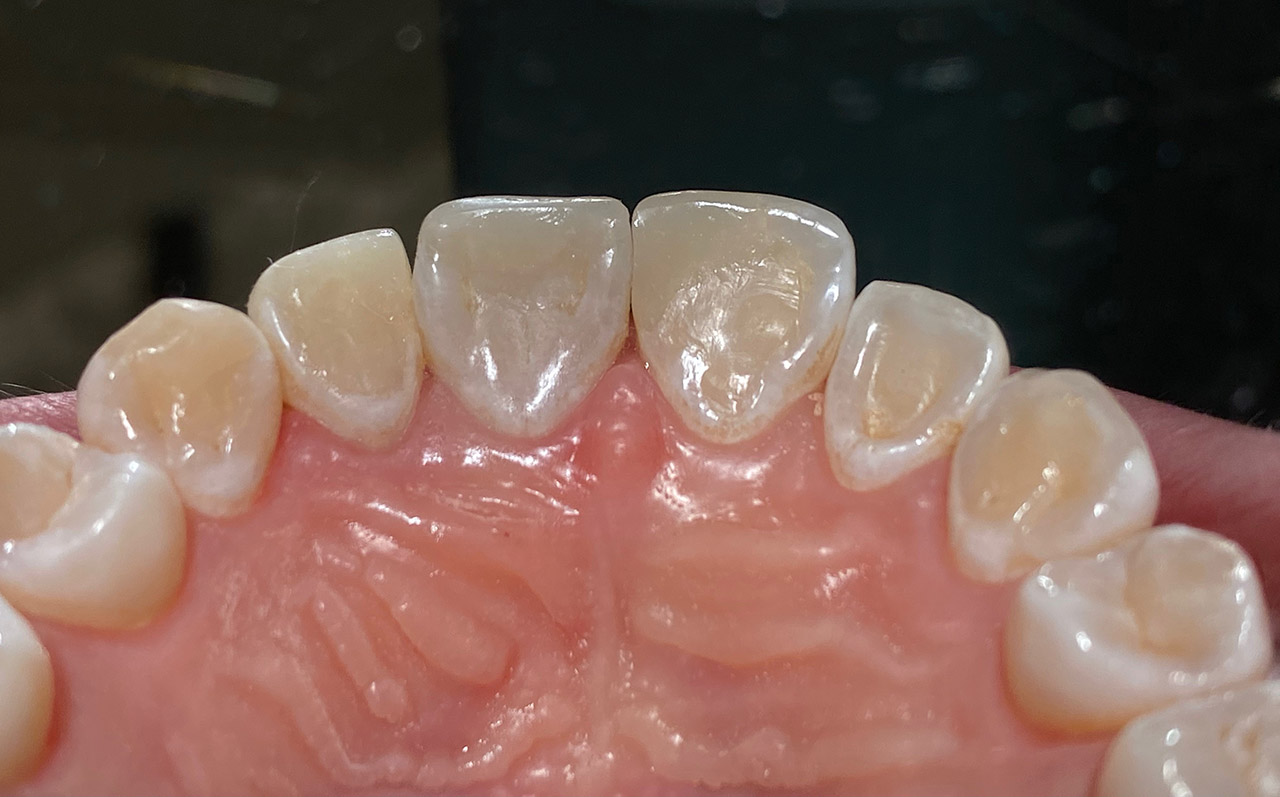

Traumatologie und Endodontie:

Nach Unfall/Sturz mittlerer Schneidezahn auf Gingivaniveau abgebrochen, Pulpa weit eröffnet, beide Nachbarzähne ebenfalls frakturiert.

Erstversorgung: Pulpektomie der Kronenpulpa, MTA, provisorischer Verschluß mit rosa Glasionomerfüllung.

Wiederaufbau der Nachbarzähne mit mitgebrachten (plus 1 Stein) Zahnstücken mit Kunststoff ergänzt und adhäsiv verklebt.

2. Schritt nach Aushärtung von MTA: Entfernung der Kronenpulpa im Bruchstück zur Vermeidung von Verfärbung, Füllung mit Kunststoff.

Adhäsives zementieren des abgebrochenen Zahnstücks.